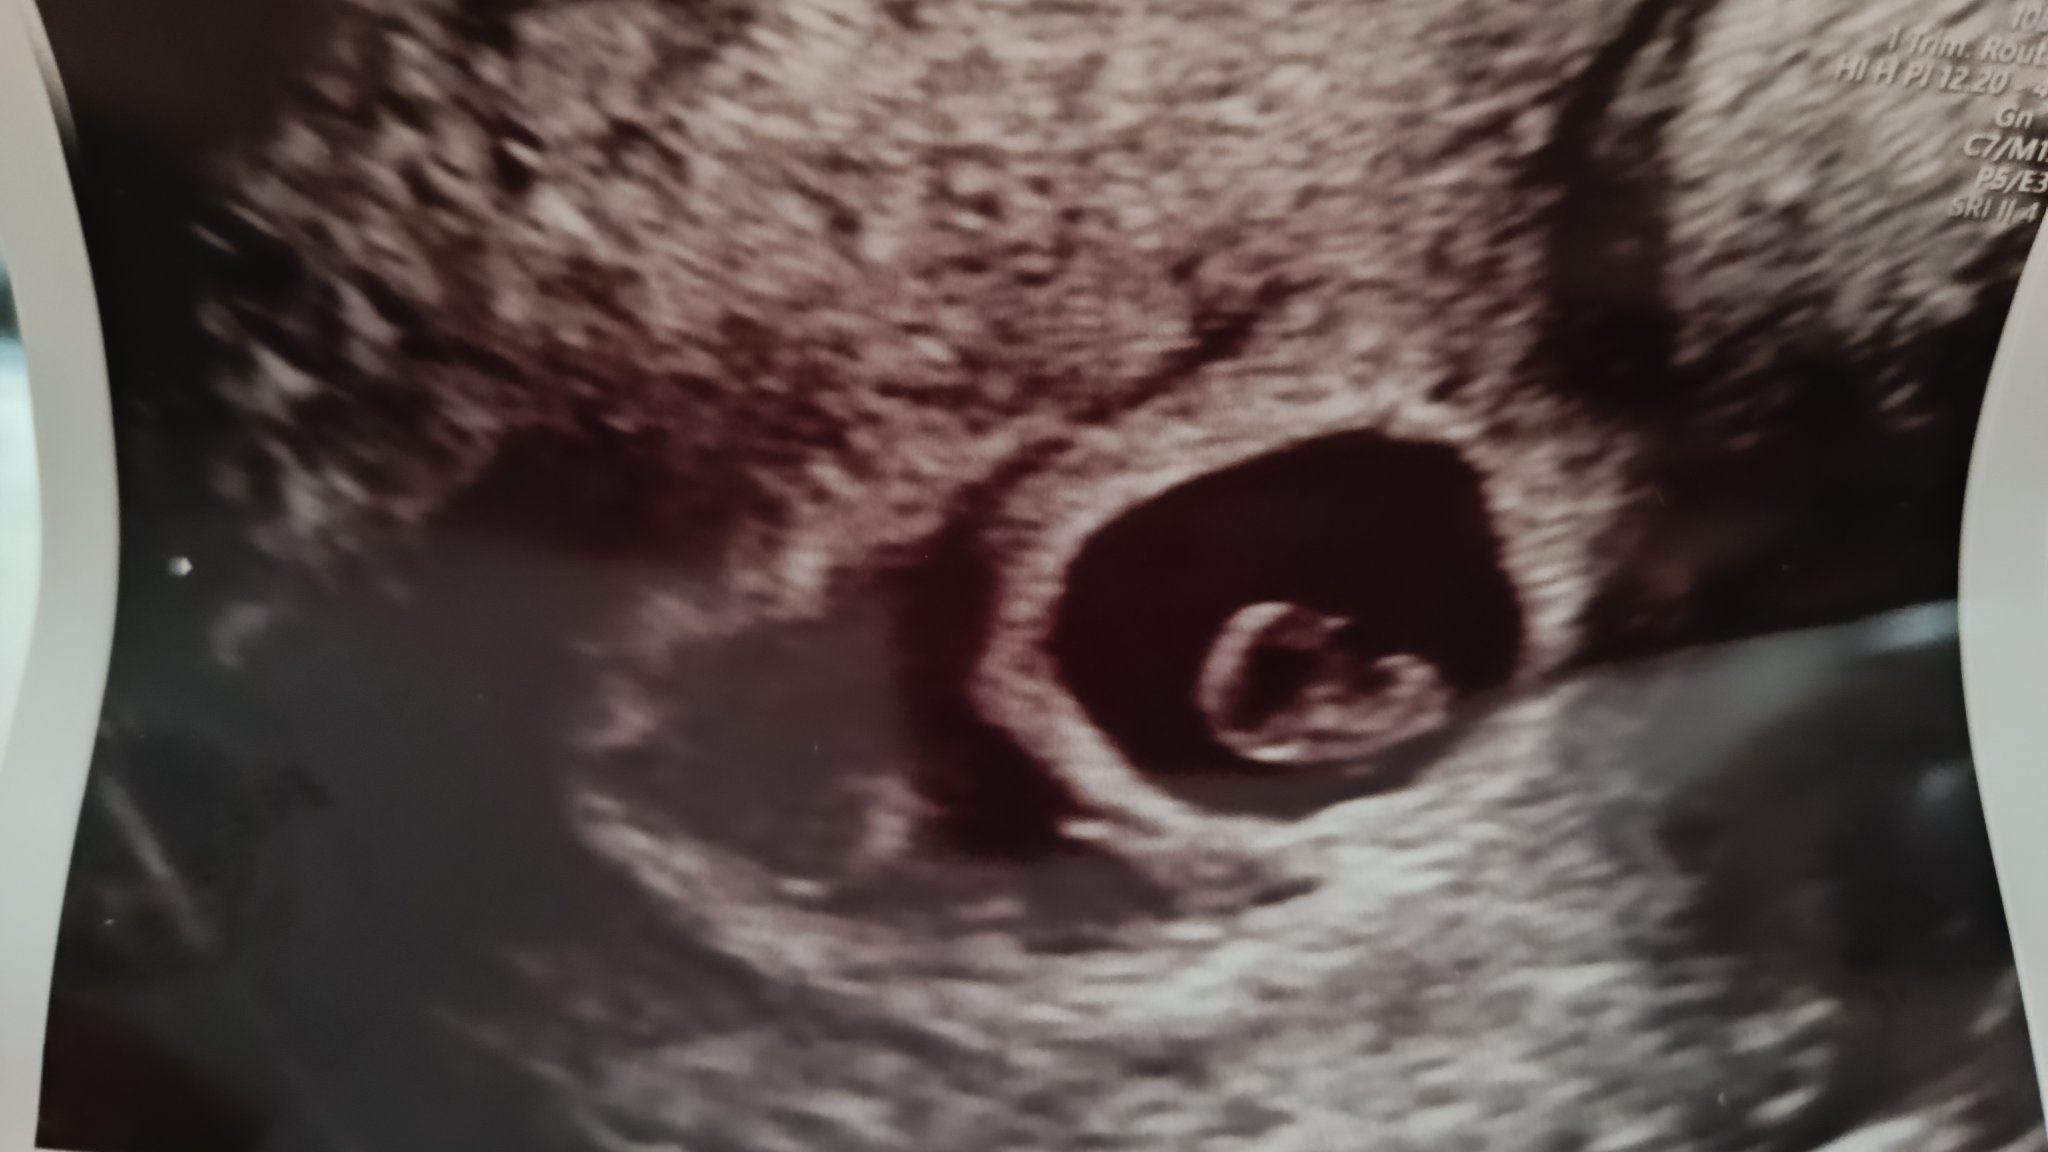

Здравейте, присъединявам се към вас плахо, тъй като съм в 6+5г.с и с отлепяне на плодния сак. Имам кафяво зацапване от около седмица. Докторът ми написа болничен и каза да почивам.

Имам нужда от кураж! По снимката ми се струва доста голямо отлепване, въпреки че доктора нищо не каза за размерите ...

Моля споделете имали ли сте отлепване в ранна бременност? Как се развиха нещата?

Здравей. Още в началото на 6г.с. имах голям хематом с отлепване, лежах и в болницата за задържане. Лежах плътно (само тоалетна и храна)  до началото на 4 - ти месец,  когато бебче се закрепи и хематома изчезна напълно.. Щом кръвта е кафява, тя  е стара и се изчистваш. Лекарят би трябвало да ти е предписал медикаменти? Най малкото прогестерон? Не мога да каже дали е голямо или малко отплеването, щом го има трябва да се пазиш и да си полежиш. Да кофти е да си повечето време на легло, но като знаеш защо, си струва всяка една минута.. Бъди спокойна и светли мисли! Всичко ще бъде наред, когато и мама се чувства добре.  Успех! Simple Smile